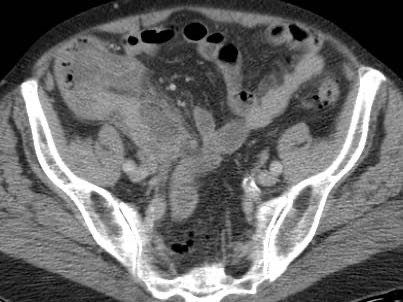

Ở người phụ nữ 56 tuổi này với CRP 180, siêu âm phát hiện dịch trong phúc mạc đục (*) và có thể thấy ruột thừa viêm với sỏi phân (mũi tên).

CT xác nhận hai sỏi phân ở hố chậu phải với hình ảnh khí bất thường, nghi ngờ viêm ruột thừa thủng.